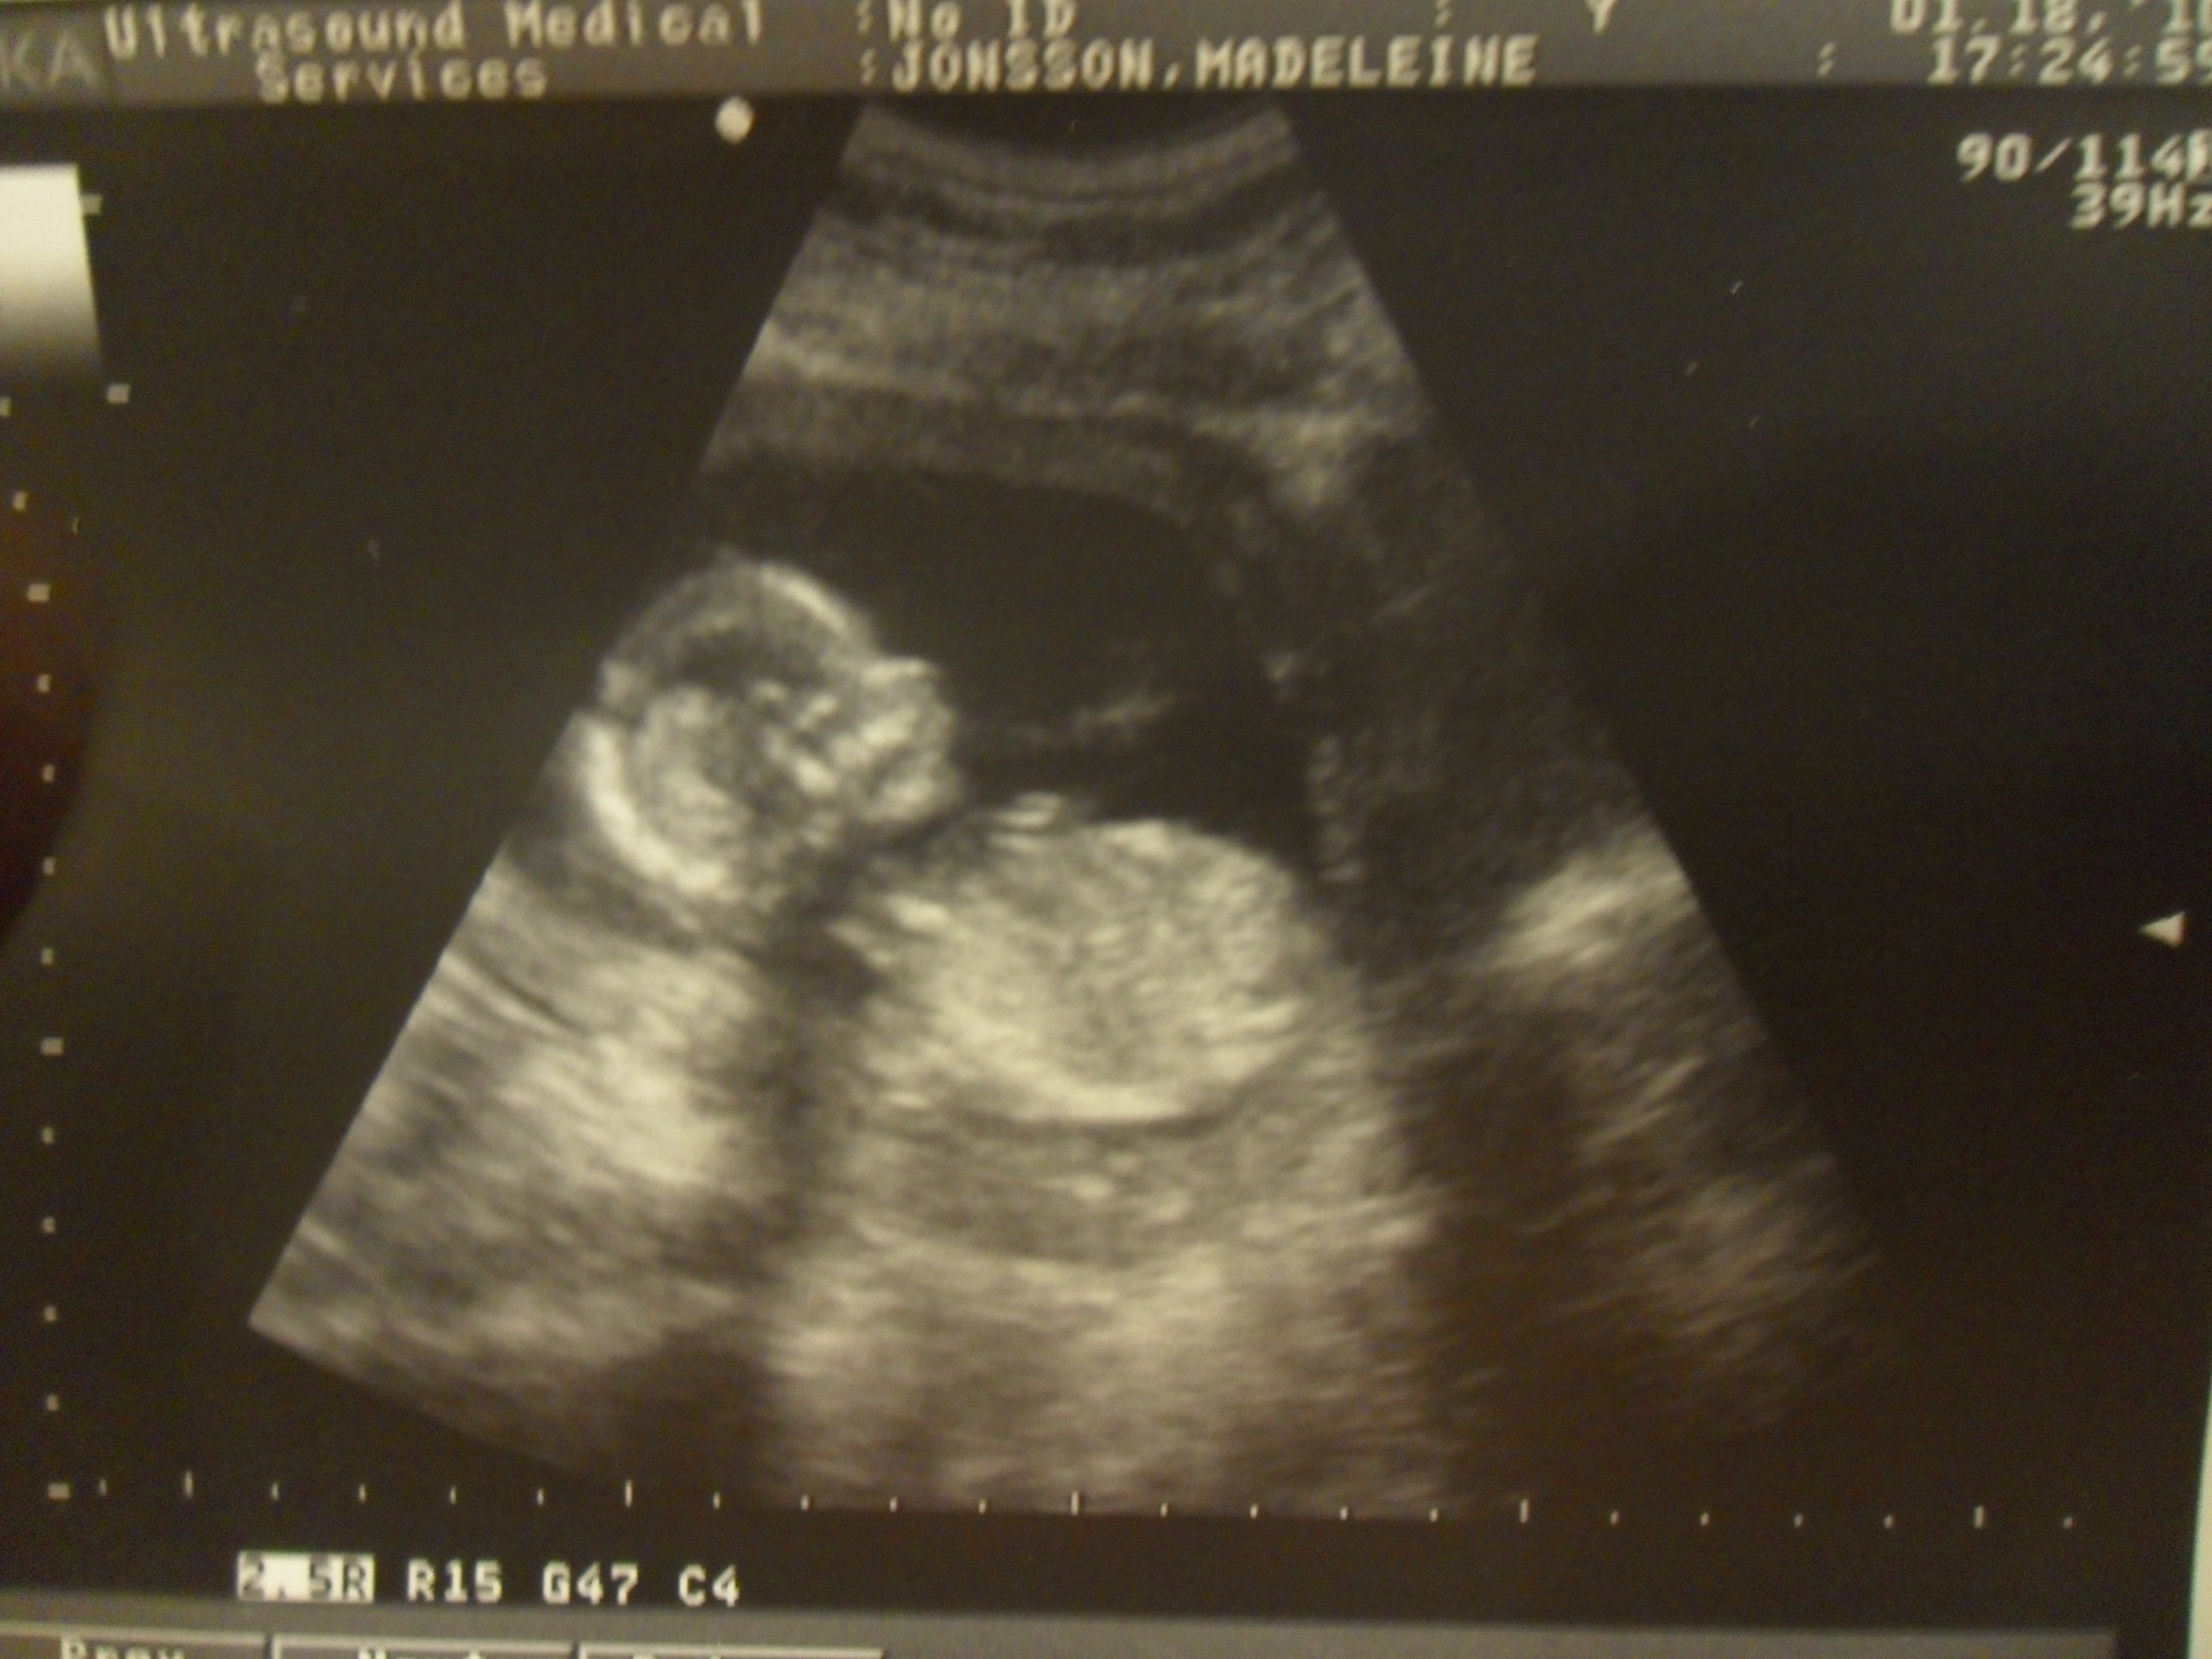

‘Ahhh Baby! Baby! Titta Baby’ 🙂 Sötisen. Först när vi satte igång så låg

navelsträngen mellan bena och de va svårt att se.. Jag fick hosta och

lägg mig på sidan för att få strängen att flytta sig. Tillslut så kunde vi

se en klar bild av hela härligheten haha.. 3 vita linjer, vilket betyder TJEJ.

Baby i profil.. Helt otroligt att den är en liten person där inne. Man kan se

örat, munne, näsan.. ja allt 🙂 Älskar dig så mycket redan lilla bönan..

skynda dig och jäs klart där inne så vi får träffa dig här ute ♥